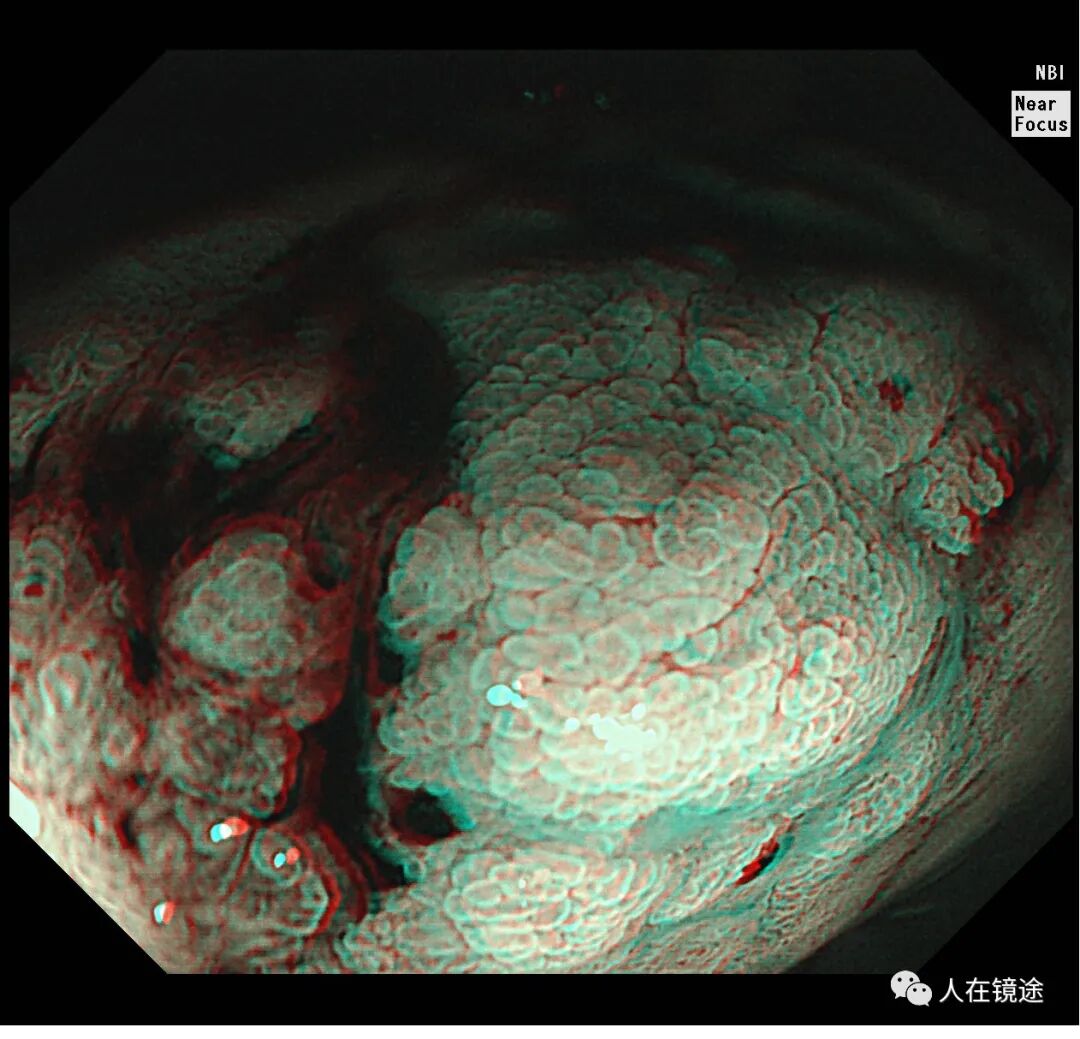

NBI+靛胭脂+近焦示:病变边界清楚,约0.8*1.2cm大小,表面粘膜高低不平,微结构紊乱伴自发性出血

靛胭脂+醋酸示:病变边界清楚,约0.8*1.2cm大小,表面粘膜高低不平,微结构紊乱伴自发性出血,中央见腺管密集不规则,

NBI+靛胭脂+醋酸+近焦示:病变边界清楚,约0.8*1.2cm大小中央见腺管密集不规则伴自发性出血。